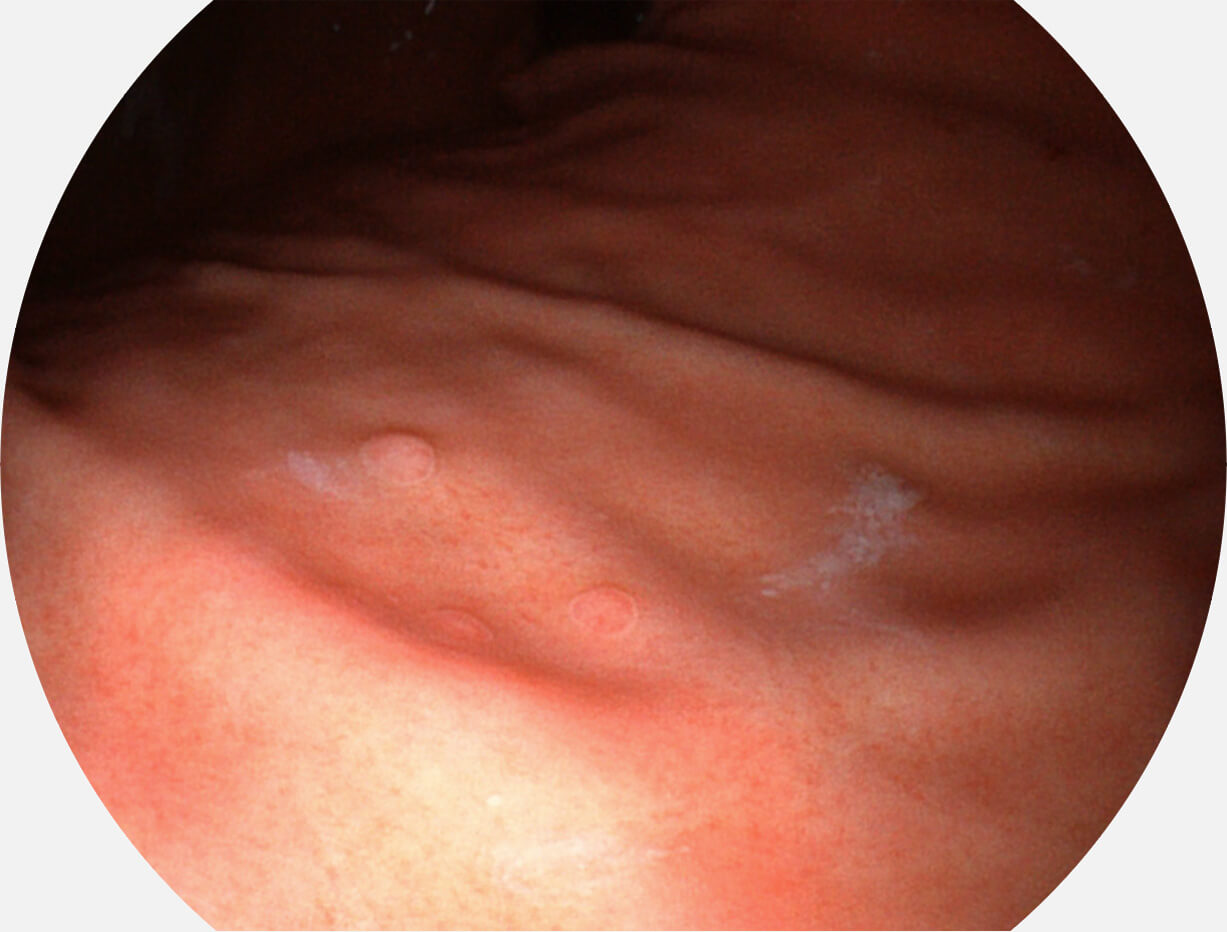

Spectral Focused lmaging, SFI

图像具有高亮度、高黏膜血管颜色对比度的特点,且不改变粘液、食物残渣、粪便的基本颜色,可在中远景下进行观察,助力消化道早期疾病的诊断。

SFI图像